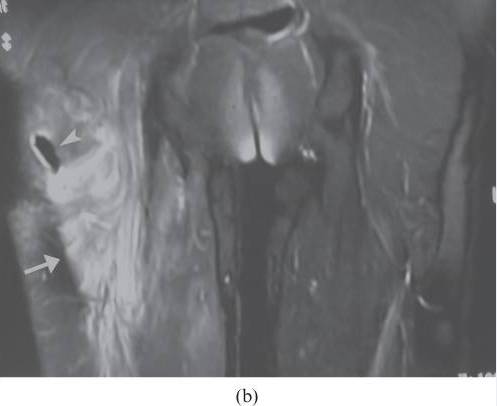

![]()

图24.骨骼肌损伤和肌坏死。 该患者,在坠落后发生的右大腿中的受污染伤口导致感染性肌坏死。 (a)轴向T2加权MRI图像显示肿大的内收肌和股二头肌----(肌肉)由于水肿扩散高信号强度。 在大收肌(箭头)中看到中心区域与流体聚集相一致。 (b)冠状动脉脂肪抑制T2加权磁共振成像显示弥漫性水肿在大腿近端的后房(箭头)。 其信号空隙肌内气体被看作指示严重感染(气性坏疽)的存在(箭头)。 感染区域的培养物显示破伤风杆菌。